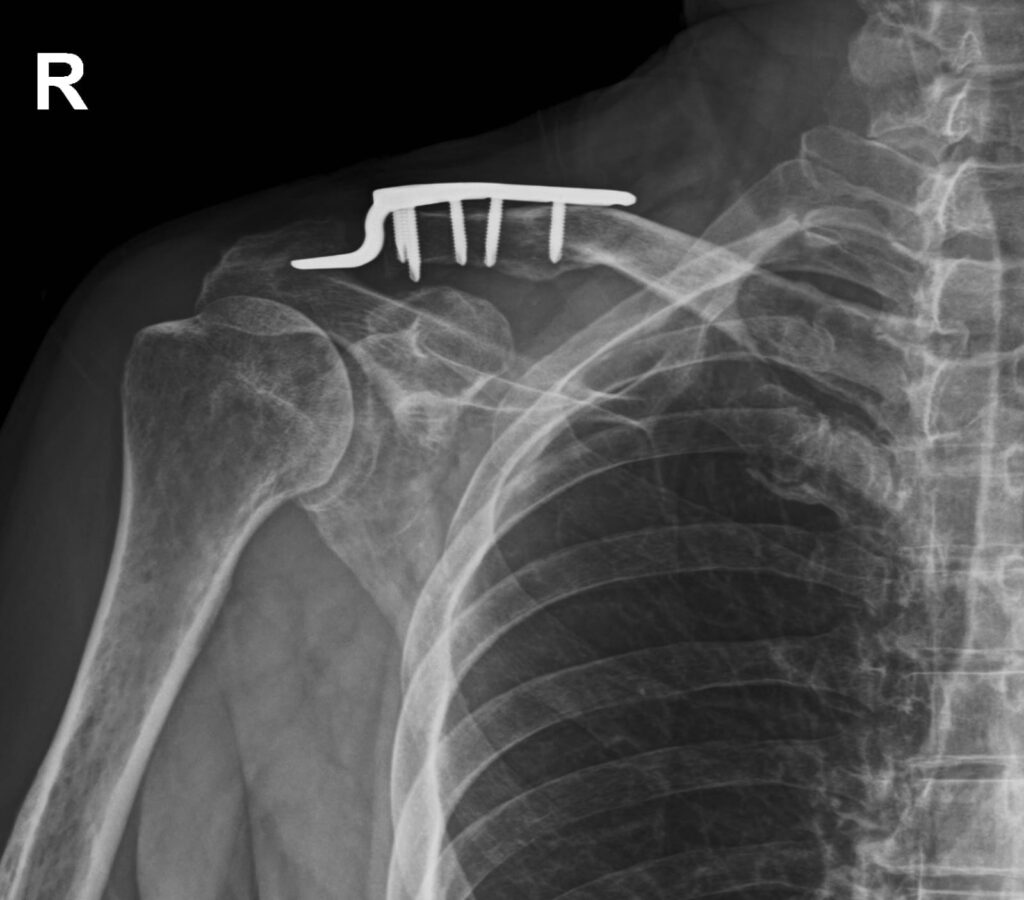

The patient presented to our clinic following surgical treatment for a classic Tossy III acromioclavicular joint injury, reporting persistent pain and significant limitations in shoulder mobility. Initial clinical assessment demonstrated marked restrictions in shoulder flexion, abduction, as well as internal and external rotation. Based on the severity of the functional impairment, a demanding rehabilitation process was anticipated.

Over a rehabilitation period of approximately four months, shoulder function was restored to approximately 90% of the pre-injury level. At the final stage of rehabilitation, surgical hardware removal was performed to facilitate full functional recovery of the shoulder joint. The patient subsequently followed a highly specific, progressive active rehabilitation protocol aimed at optimizing neuromuscular control and enabling a safe return to sport.